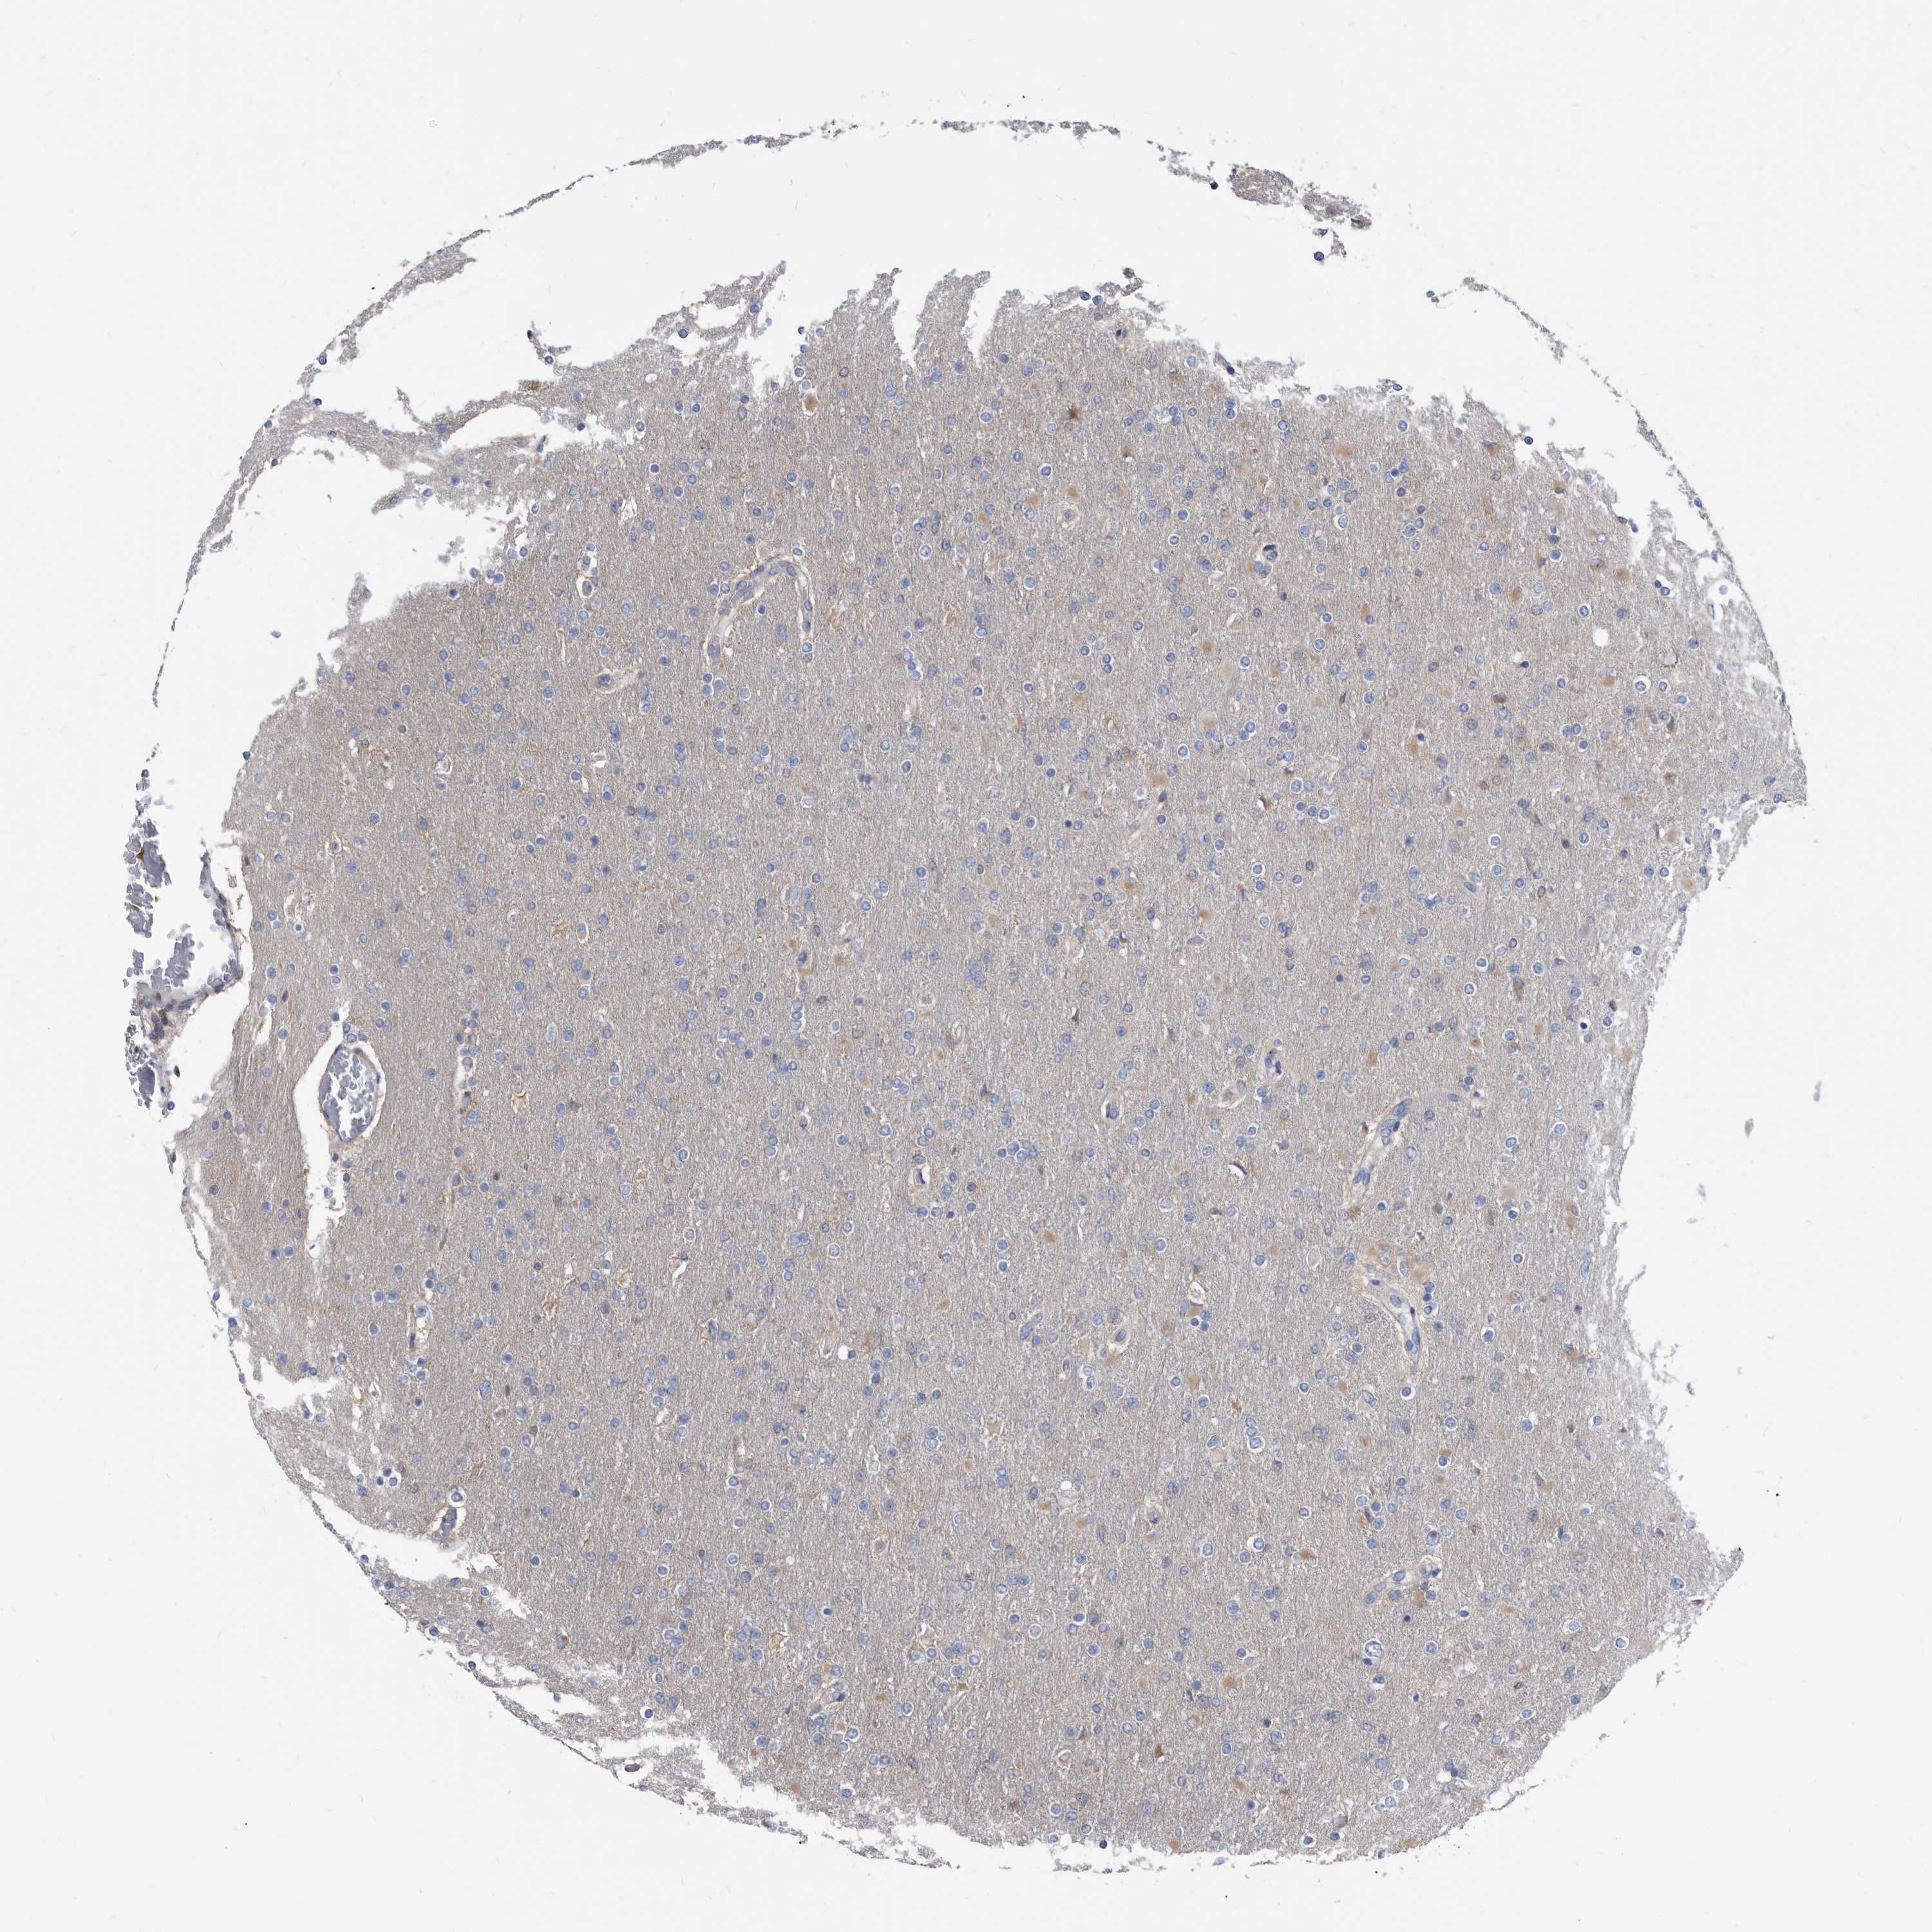

GLIOMA - Protein expressioni

A mouse-over function shows sample information and annotation data. Click on an image to view it in a full screen mode. Samples can be filtered based on level of antibody staining by selecting one or several of the following categories: high, medium, low and not detected. The assay and annotation is described here.

Note that samples used for immunohistochemistry by the Human Protein Atlas do not correspond to samples in the TCGA dataset.

Antibody stainingi

Antibody staining in the annotated cell types in the current human tissue is reported as not detected, low, medium, or high, based on conventional immunohistochemistry profiling in selected tissues. This score is based on the combination of the staining intensity and fraction of stained cells.

Each image is clickable and will lead to virtual microscopy that enables deeper exploration of all samples and also displays staining intensity scores, fraction scores and subcellular localization as well as patient and tissue information for each sample.

Antibody HPA029700

Antibody HPA029701

Antibody HPA029702

Antibody HPA029703

Staining

High

Medium

Low

Not detected

Intensity

Strong

Moderate

Weak

Negative

Quantity

>75%

75%-25%

<25%

None

Location

Nuclear

Cytoplasmic/membranous

Cytoplasmic/membranous,nuclear

Glioma, malignant, High grade

Glioma, malignant, Low grade

Glioblastoma, NOS